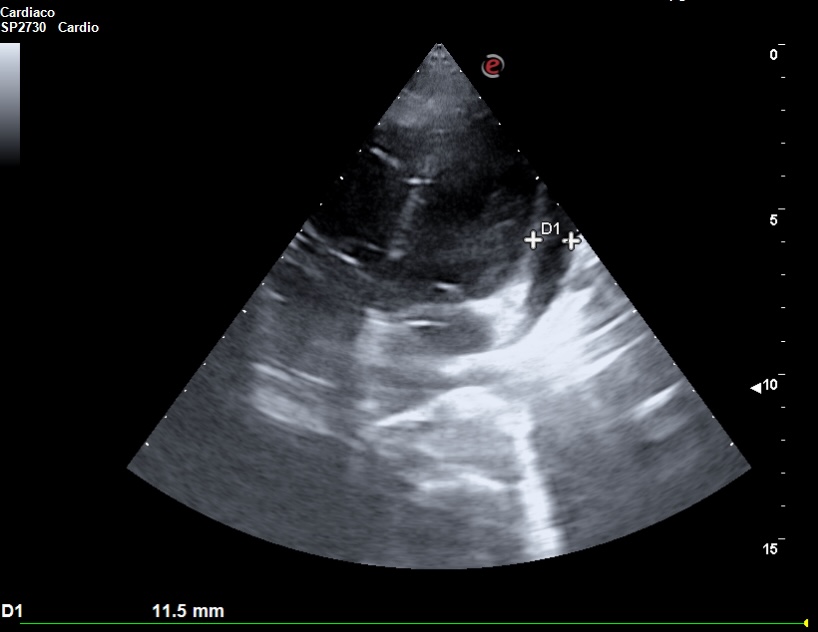

La ecocardioscopia mostró ventrículo izquierdo no dilatado con función sistólica conservada, sin hipertrofia del septo interventricular ni valvulopatías. Aurículas izquierda y cavidades derechas de tamaño normal. TAPSE normal. Se evidenció un derrame pericárdico moderado sin signos de taponamiento cardíaco. Calibre de vena cava inferior normal con colapsabilidad mayor del 50%. Hallazgo de derrame pleural derecho moderado.

La ecografía clínica desempeñó un papel fundamental en la evaluación inicial del paciente, permitiendo una detección rápida y precisa de hallazgos que guiaron la toma de decisiones clínicas. La ecocardioscopia realizada reveló un derrame pericárdico moderado, sin signos de taponamiento cardíaco y un derrame pleural derecho significativo. Estos hallazgos fueron esenciales para descartar la presencia de un cuadro obstructivo que pudiera haber requerido una intervención inmediata. Además, la ecografía permitió valorar el estado hemodinámico de la paciente de forma no invasiva, asegurando que el derrame pericárdico no comprometiera la función cardíaca. En la radiografía de tórax se objetiva una masa mediastínica. La capacidad de detectar y cuantificar de forma precisa tanto el derrame pleural como el pericárdico sin necesidad de esperar a pruebas más complejas, permitió que la paciente fuera ingresada de manera adecuada para un estudio exhaustivo y sin demoras innecesarias.